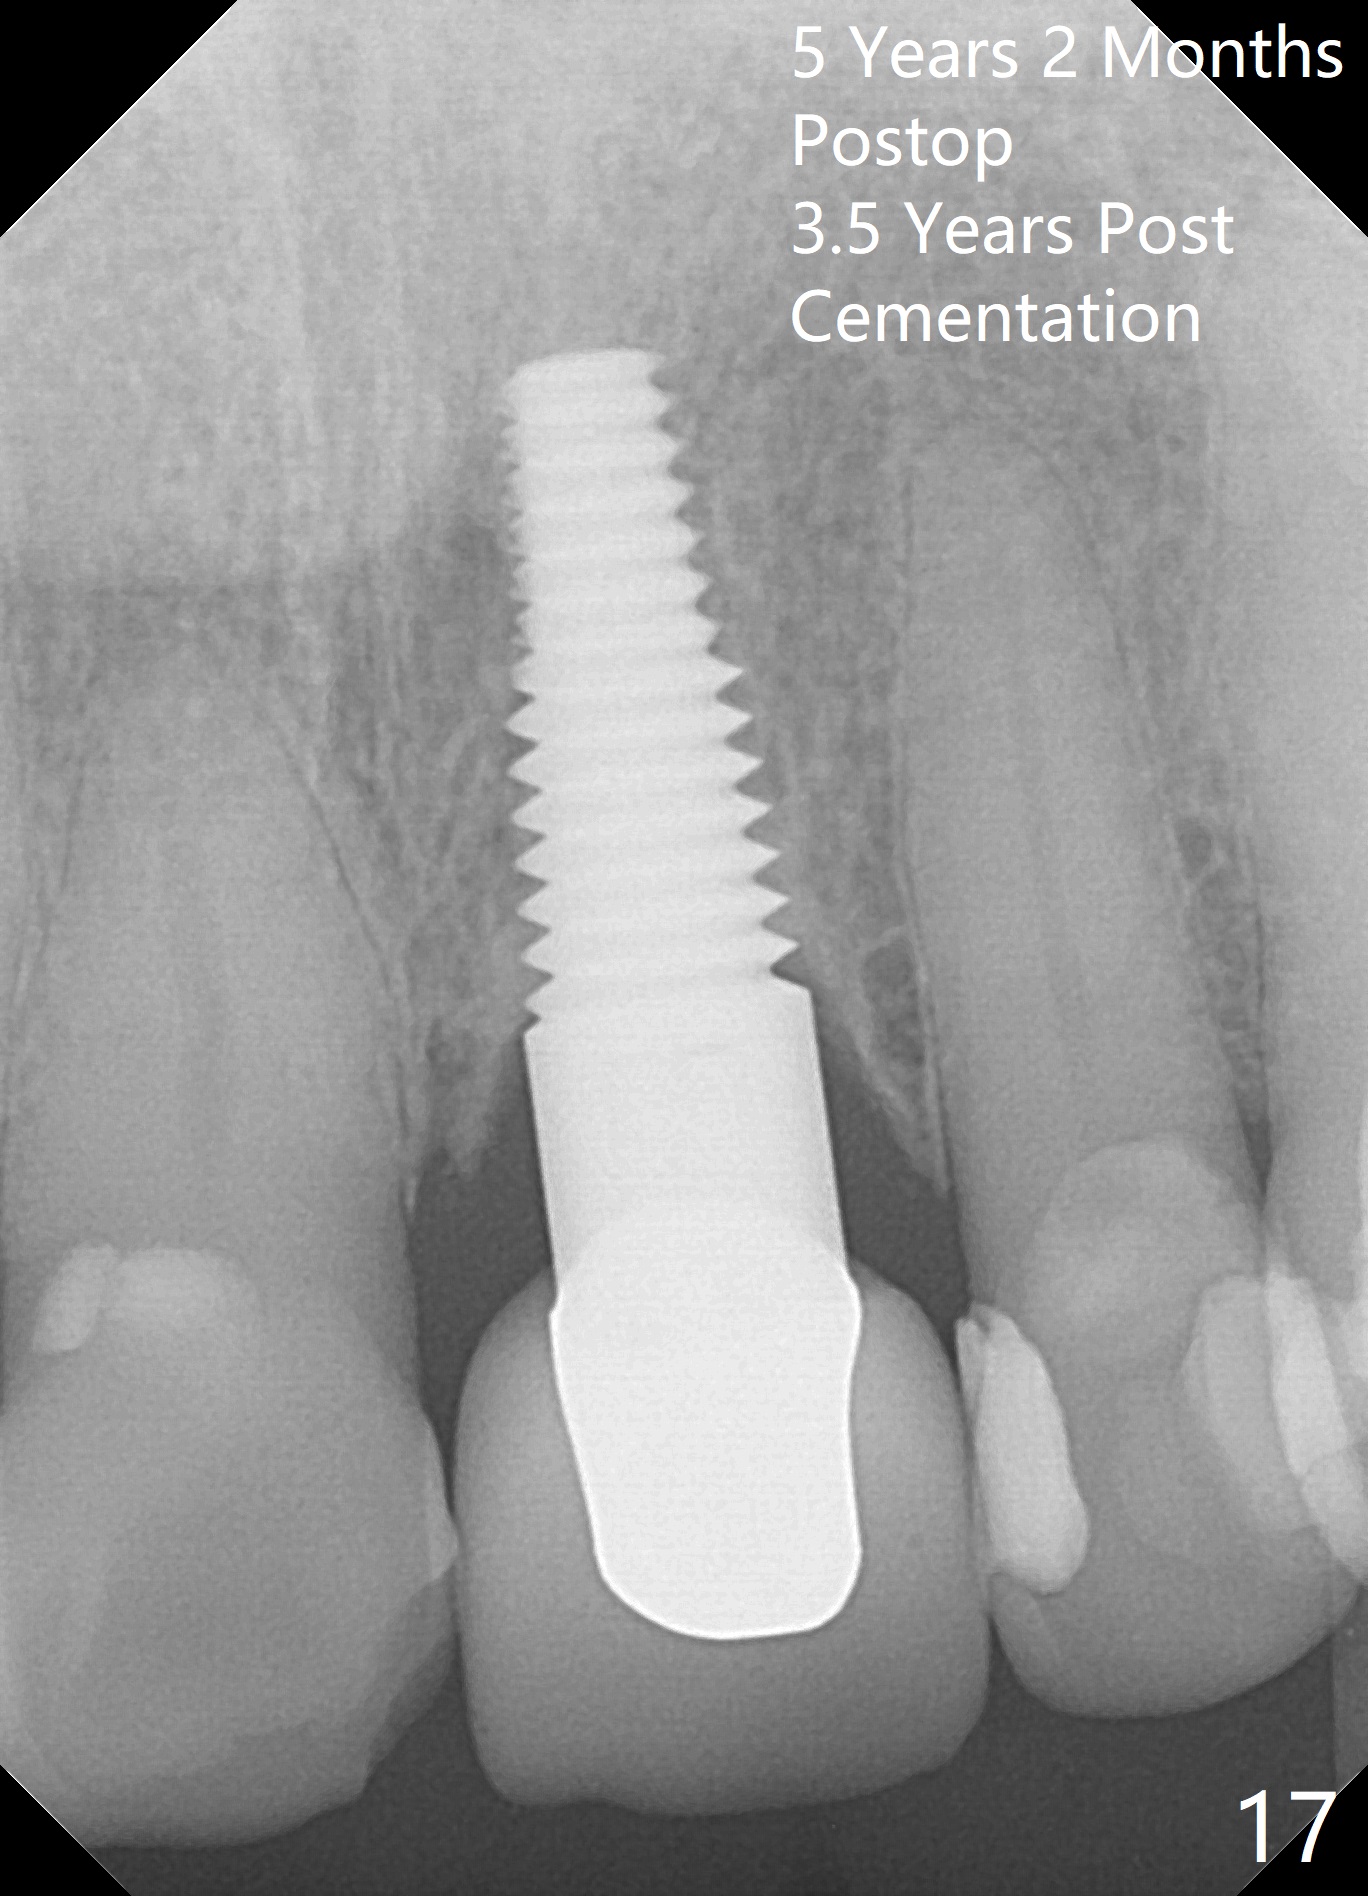

Postop tenderness lasts for two days. The palatal swelling is unnoticeable 7 days postop (Fig.9 *, as compared to A in Fig.8). The bone remains stable around the implant (Fig.10), while the gingiva healthy around the immediate provisional (Fig.11) 5 months postop. Due to insurance limit, the permanent restoration is delayed (16 months postop, Fig.12). The patient is satisfied with the function and appearance 3 years 8 months postop (21 months post cementation, Fig.13,14). PA is taken 4 years 1 month postop (2.5 years post cementation, Fig.15). The lamina dura forms from the most coronal threads (Fig.16). Although there is no bone loss around the implant (Fig.17), metal starts to show 5 years 2 months postop (Fig.18 ^), probably related to the buccal placement, too large the implant for the site or buccal plate atrophy (Fig.19).